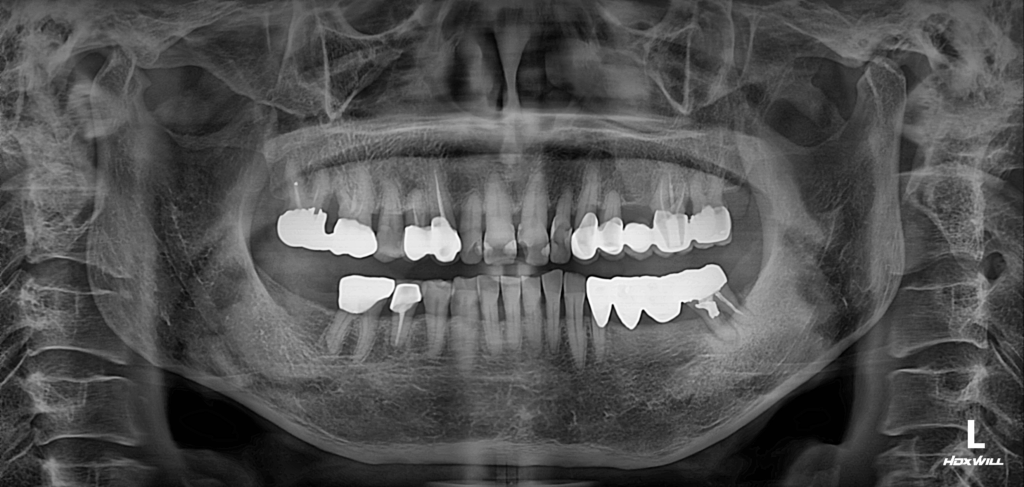

술후 사진

2024.10.25

일부 분들은 기존 보철물을 제거하고 후방에 임플란트를 삽입하면 될 것이라고 생각하실 수도 있습니다. 하지만 전방 소구치는 기능적인 역할이 큰 자연치아이기 때문에, 이를 보존하기 위해 섬세한 보철물 절단 작업이 필요했습니다. 후방 치아의 경우, 이미 주변 뼈가 많이 소실되어 있어 골이식이 필수적이었습니다.

해당 환자분은 지속적인 체크업을 받으며, 전방 소구치 부분은 현재까지도 긍정적인 예후를 보이고 있습니다. 후방 임플란트도 안정적으로 식립되어 저작 기능을 정상적으로 회복한 상태입니다.